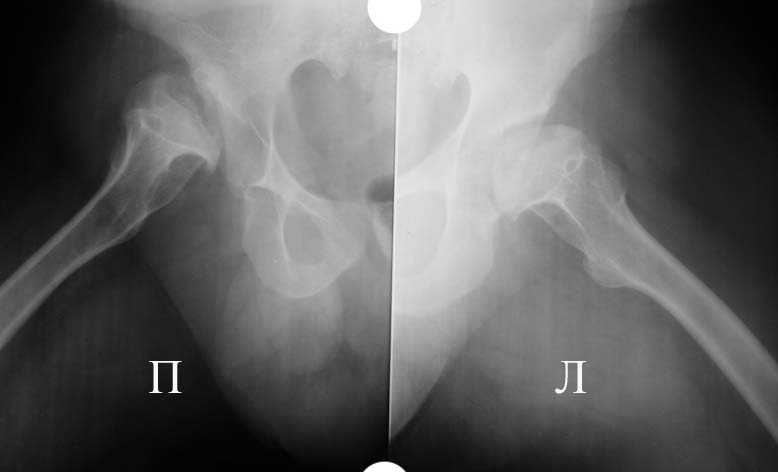

Прямая проекция т/б суставов